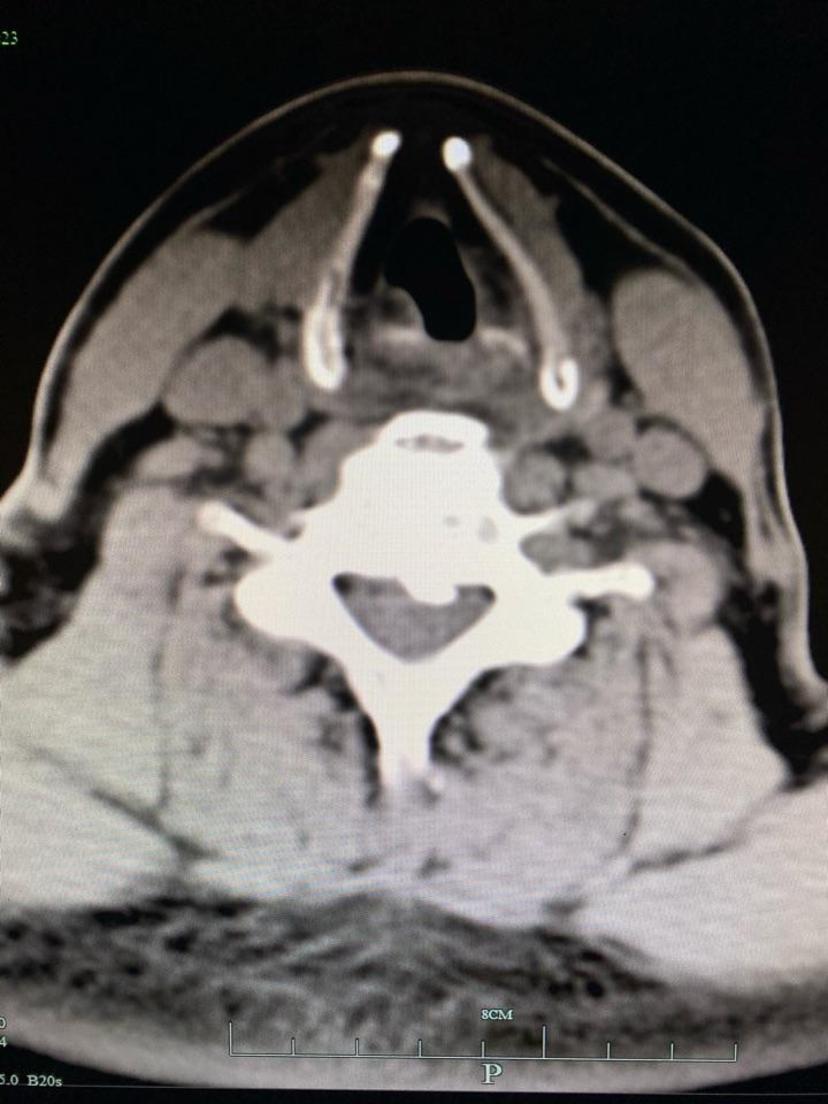

CT显示颈5-6层面后纵韧带骨化及大量骨赘

CT平扫显示压迫脊髓的骨化物